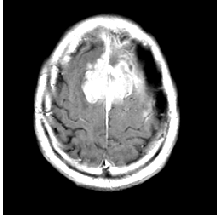

Resizing: It is the process of changing the scale of the images so that all the samples in the training and testing data sets are of the same resolution. This is required because, in the classification models, we must provide input of the same size. The images are resized to 150×150150150150\times 150 pixels using the using Numpy squeeze function for each MRI data, as shown in Fig. 2.

Refer to caption

Figure 2: Example of resizing an MRI image.